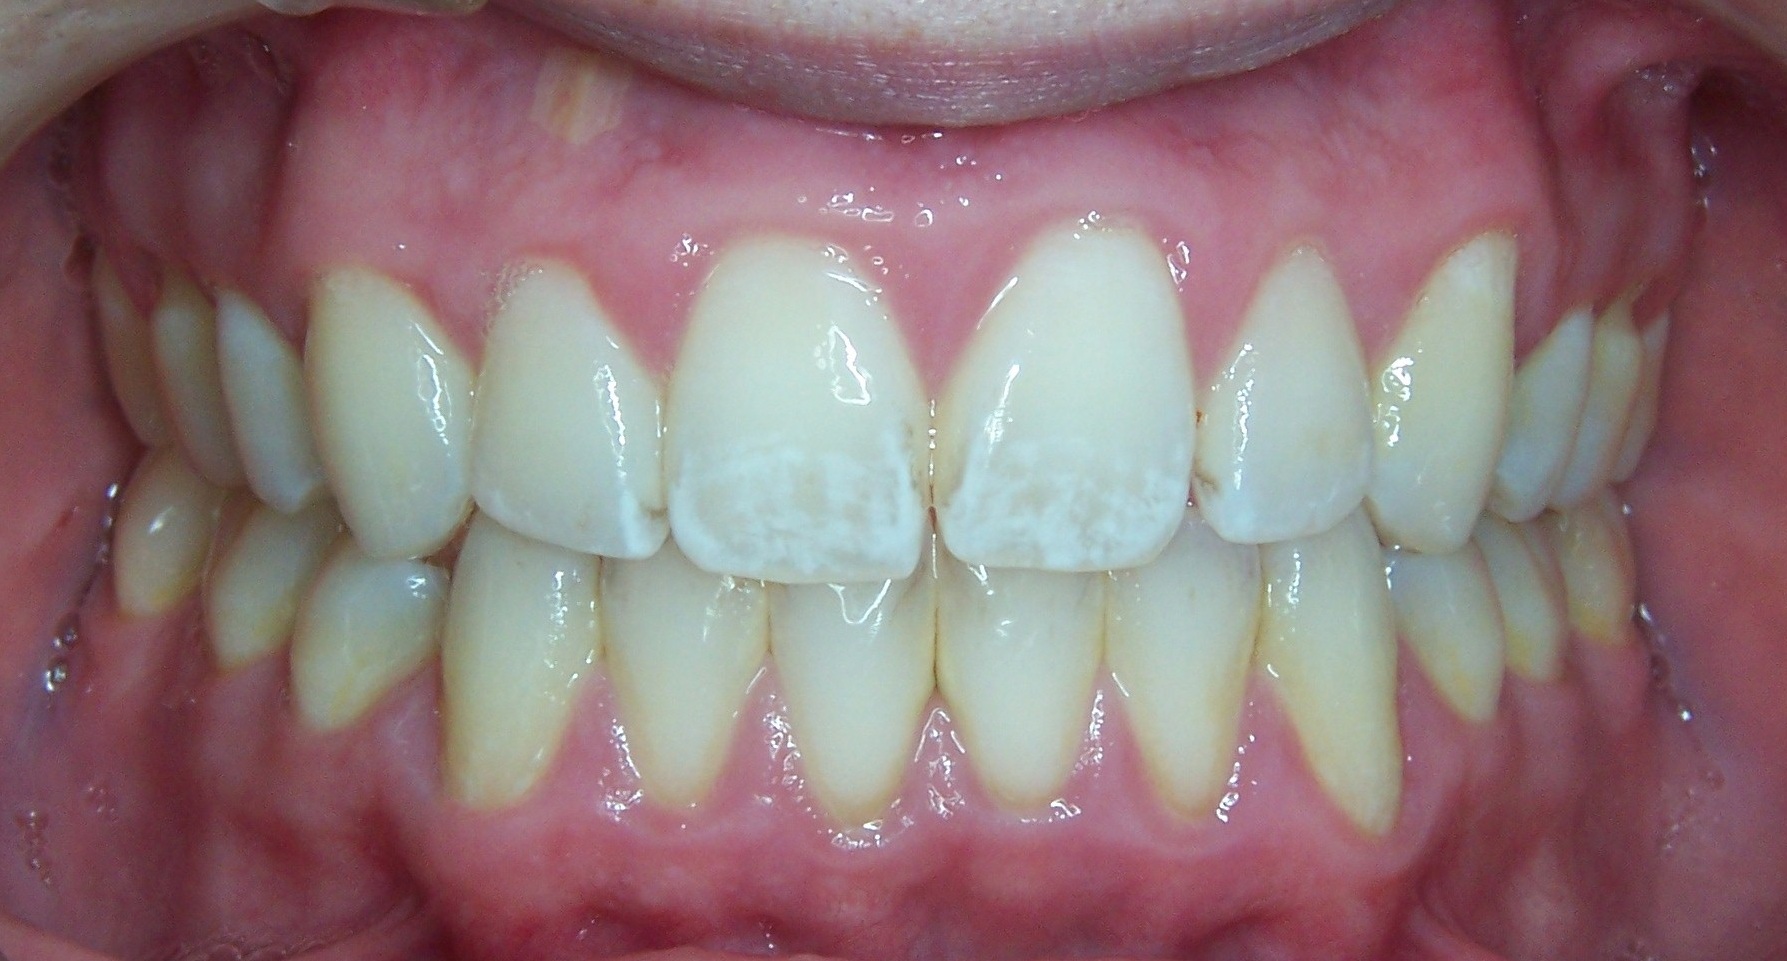

На фотографии зубы с кариесом в стабилизированной форме – наличие темных, светло-коричневых или бурых пятен.

Следует отметить, что стабилизированная форма кариеса в стадии пятна относится к медленно прогрессирующим формам кариозного поражения, следовательно, кариозное пятно длительный период времени остается стабильным и не трансформируется в кариозную полость. При отсутствии клинических показаний такое пятно требует постоянного контроля, к его препарированию и последующему пломбированию приступают только в том случае, если кариозное поражение активизируется или покрывает более 1/3 поверхности зуба.